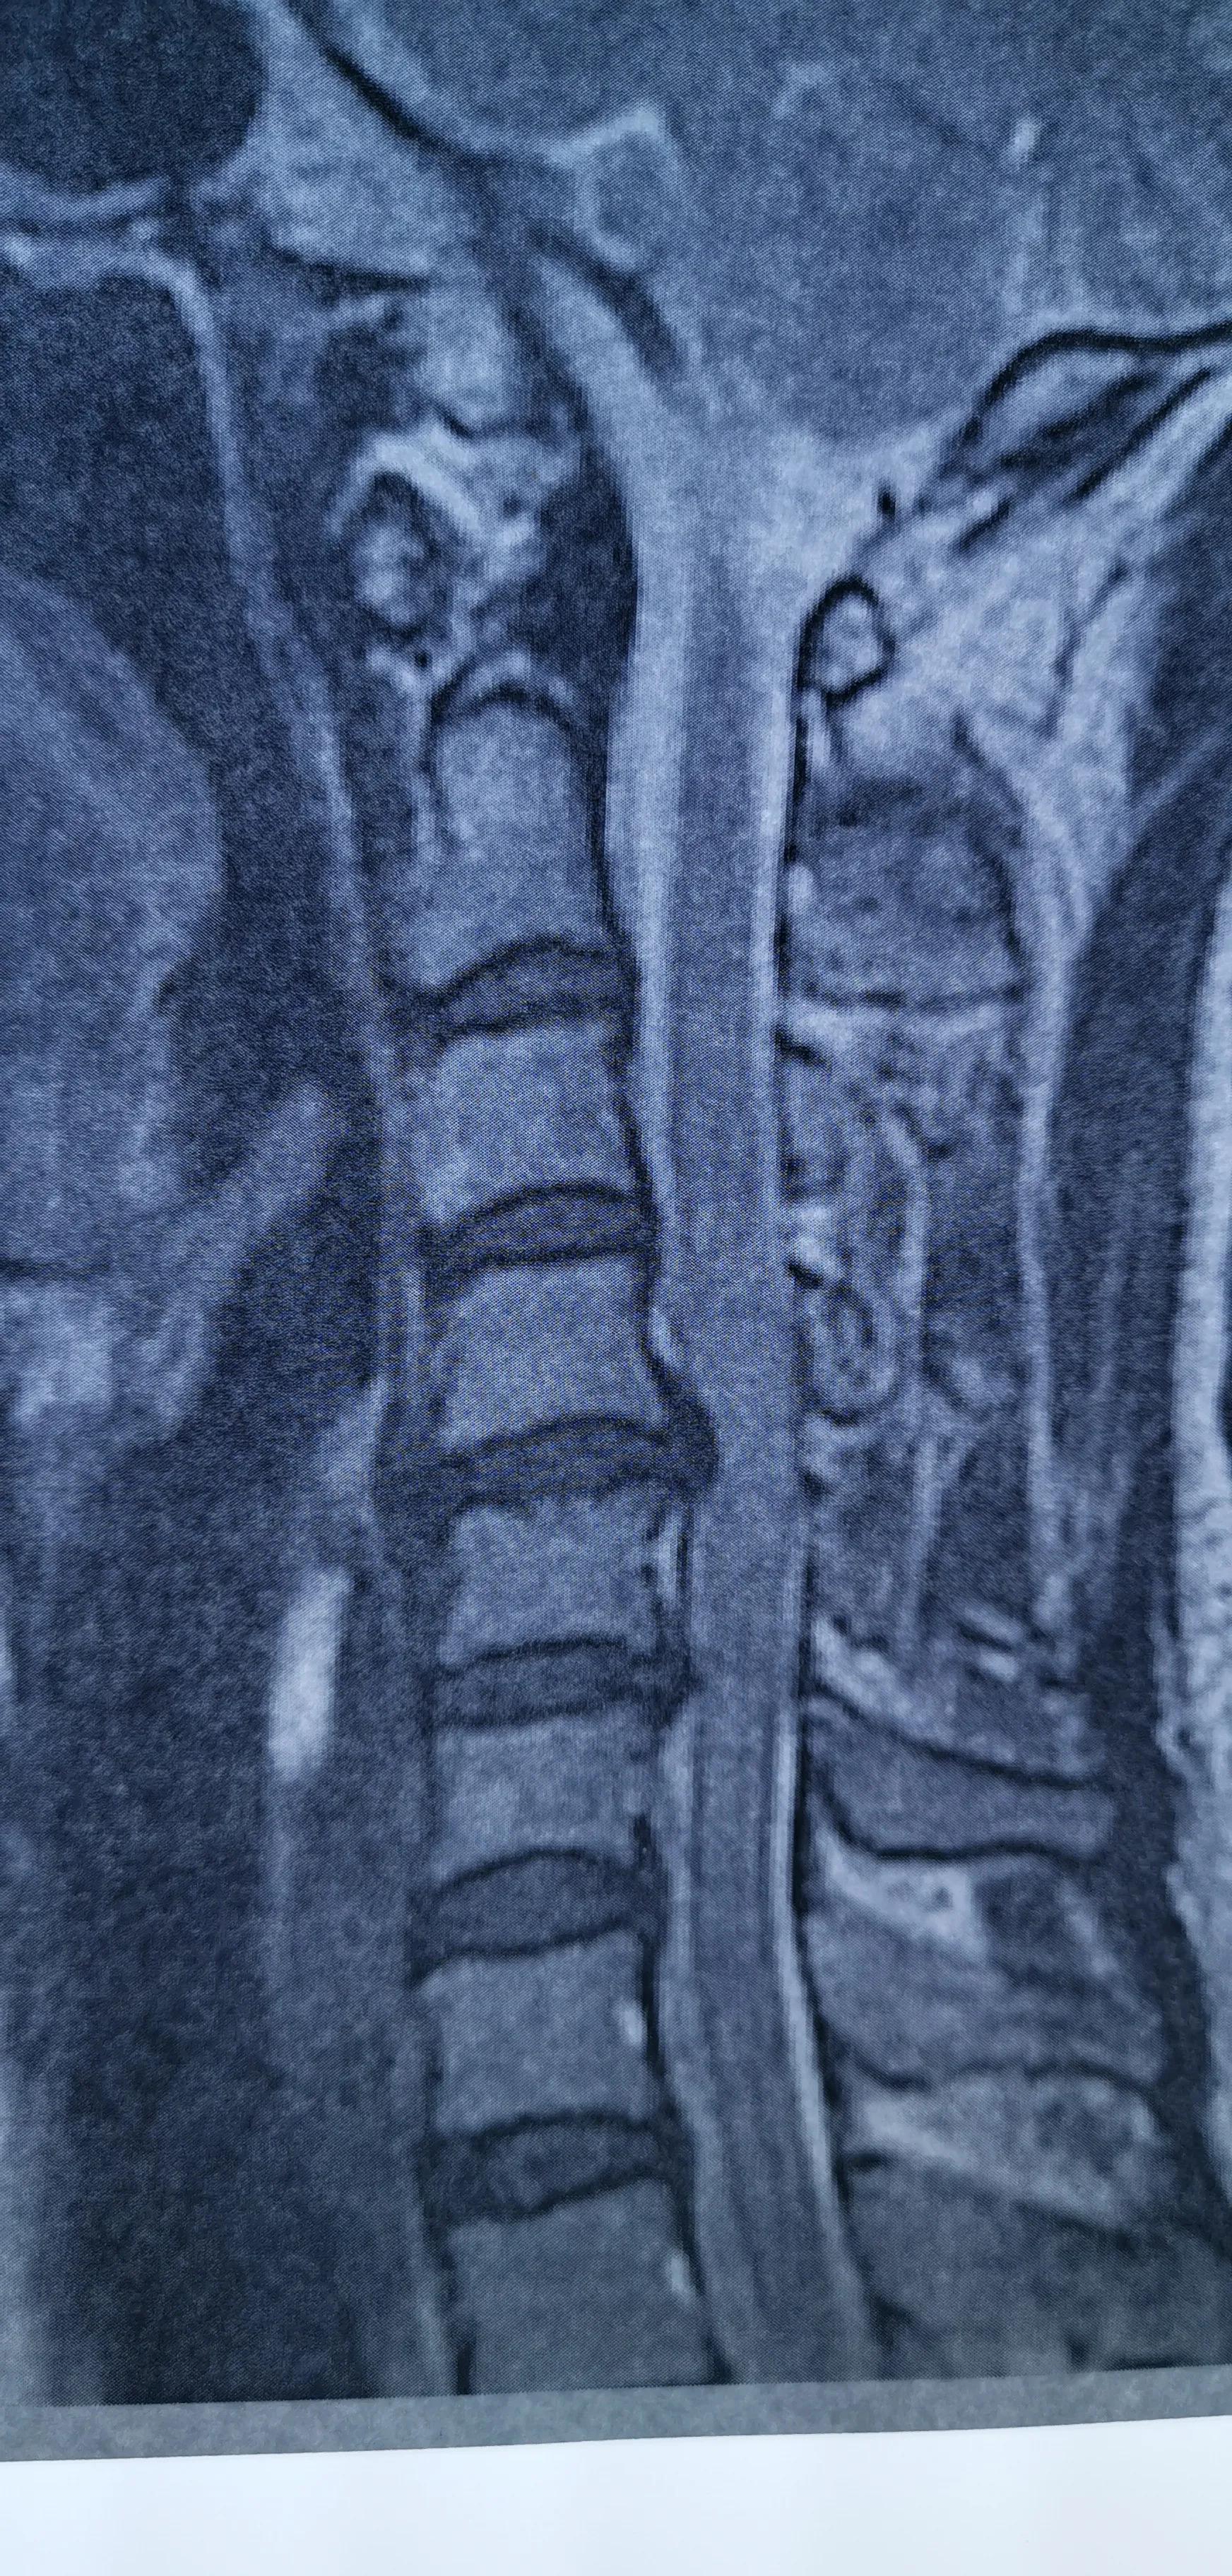

43岁女性,颈肩部疼痛严重伴左侧上肢放射痛无力,mri提示C4/5,C5/6椎间盘突出,CT提示钙化。予前路C5椎体次全切除,椎间盘摘除,椎间钛笼植骨融合钢板内固定,术后疼痛基本消失,肌力逐渐恢复,麻木缓解。

对这类椎间盘突出钙化的患者如果疼痛严重或伴肌力下降或行走不稳,提示压迫神经或脊髓,不宜推拿,可手术减压,效果显著。